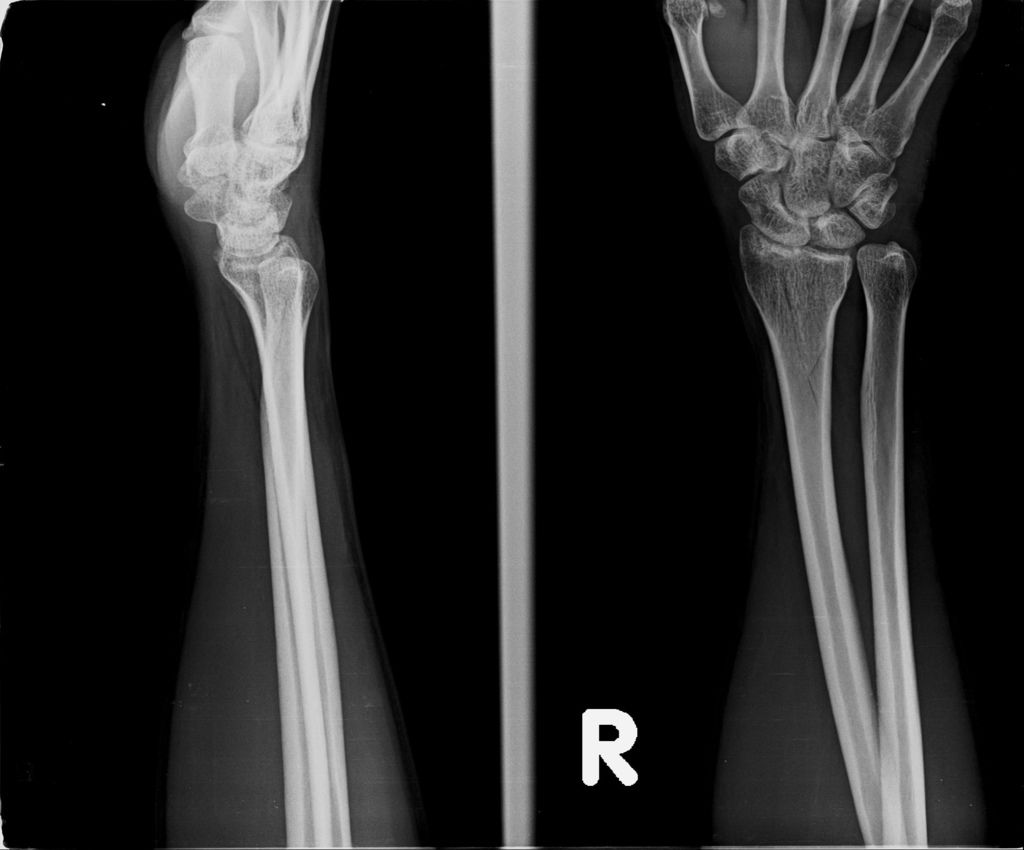

歸還完拐仗之後,至批價、掛號處,之前三次來看診,都是坐輪椅搭電梯,今天總算可以搭乘手扶梯了,讓我有點感動。繳完錢之後,接著去照X光,之前都照手和腳,從今天起腳不用照了。照完之後就去候診了。前兩次的回診,手的部份黃醫師都跟我說沒什麼變化,我聽了都感到很喪氣,也深怕今天看完診後,又得到同樣的回覆。

或許今天是228放假日,來醫院看病的人蠻多的,我們等了一段時間才被叫到。進到診間後,黃醫師調出X光資料,發現橈骨已癒合很多了,讓我感到很吃驚,兩個星期前還是很明顯的骨裂,現在已經看不太到了(小純說,一定是峰王膠原飲發揮了功效,這兩週內,膠原蛋白喝了八罐了)。黃醫師說,我的手腕護具可以拿掉了,我拿起護具後,黃醫師拉了我的手腕做一些轉動的動作,還是有些痛,黃醫師叫我要多做熱敷,手可以開始做復健了,也可以讓手開始做一些事情,但避免提重物,兩個星期後再回診看角度。

今日所拍的X光照↓

這三次回診的X光片,相較前兩次,今天已經癒合許多了↓